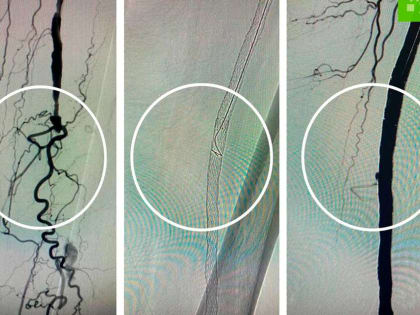

В Волгограде врачи спасли женщину от ампутации ноги

Женщина, страдающая серьезными заболеваниями, жаловалась на боль в стопе.